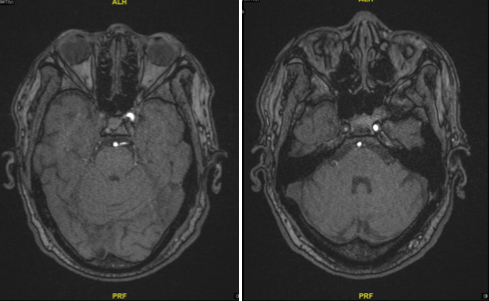

图1 MR提示存在陈旧性脑梗死,无新发梗死

图4 TOF像显示岩骨段慢血流

图5 眼段可见正常管腔,血管负性重构

图6 M1段血管存在